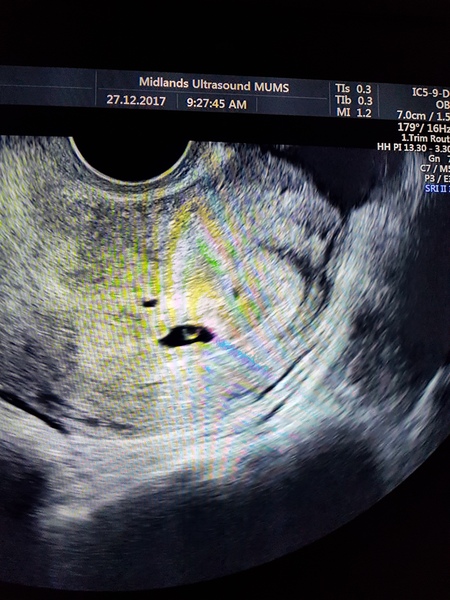

I've got 2 scans booked- the 27th and 28th. The 27th is private which we booked as I ruptured on 6 weeks and I was scared the nhs would refuse to scan earlier.

I will be exactly 5 weeks on the 27th so they warned me they may not see anything and there won't be a heart beat yet but they normally offer to scan from 5 +2. For me I also wanted to be sure I could see it, it upsets me that I never got to see my baby last time.

Sammyclaire22 · 27/12/2017 15:47

Exactly 5 weeks today and my little sprout is where it should be :) Only saw the gestational sac and yolk sac but that's normal for this early. Way to go right ovary!! (She could tell on the ovary from the follicle that it had produced the egg this time)